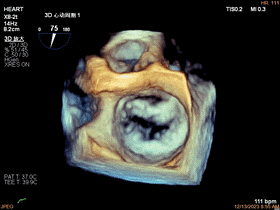

二尖瓣的外科视角——主动脉瓣在12点位